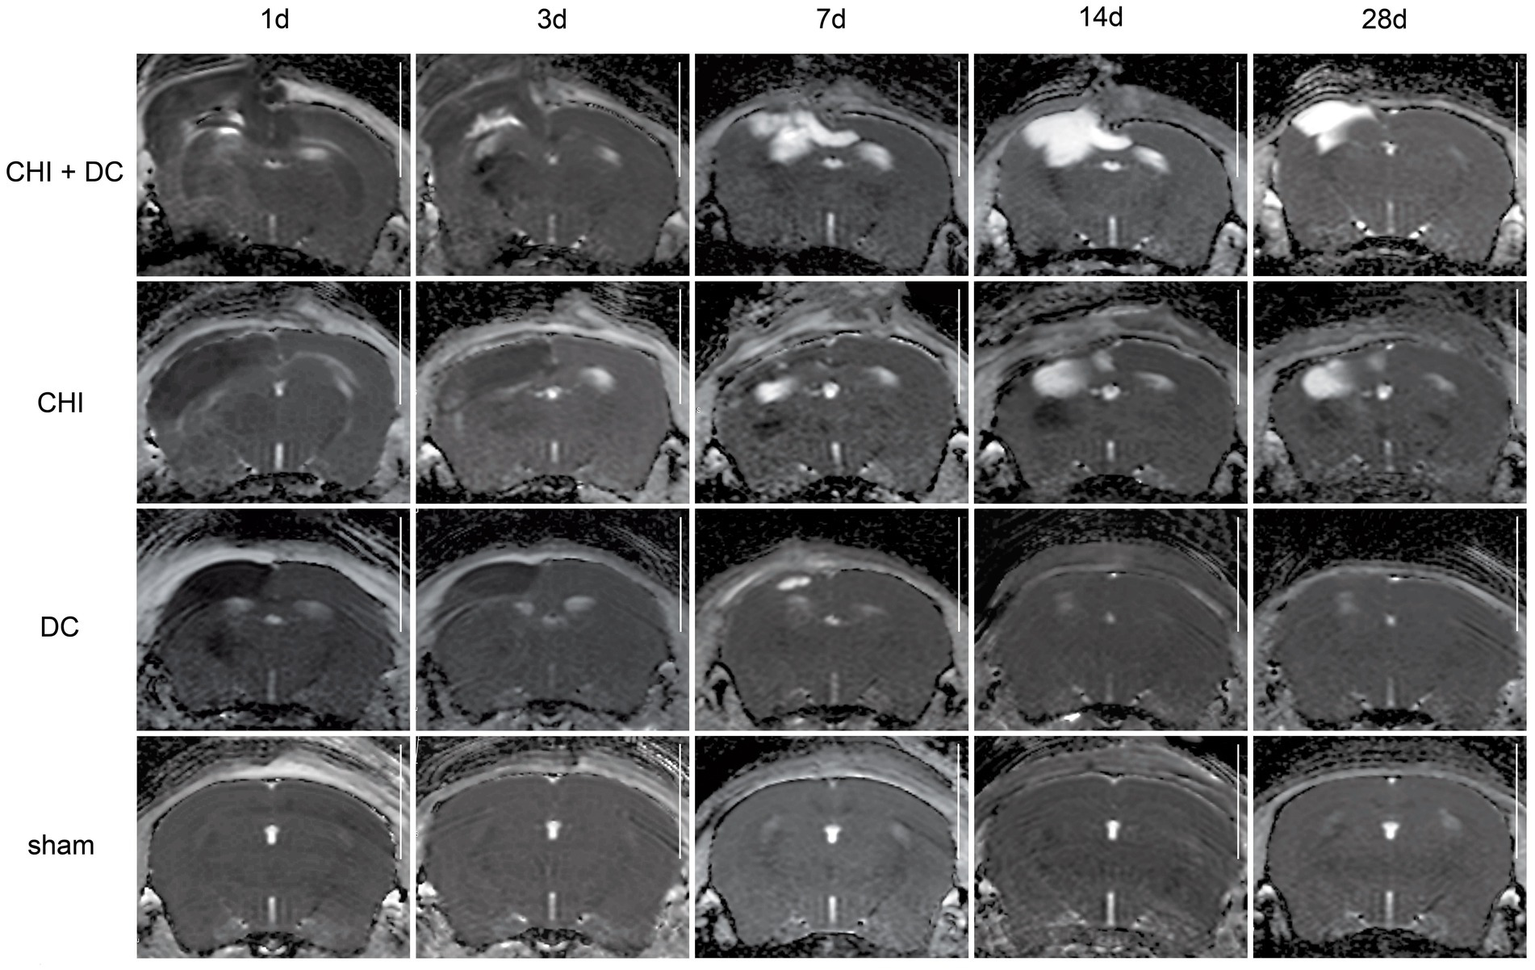

Set of images similar to Figure 5, including T2-MRI scans. See description and interpretation of radiological changes in the main text. Again, the scans were obtained in representative animals (each row demonstrates the radiological course in the same animal) using a 9.4 Tesla MRI scanner; white bar = 5 mm.

Figure 7

Set of images similar to Figures 56, presenting ADC-MRI maps. See description and interpretation of radiological changes in the main text. Again, the scans were obtained in representative animals (each row demonstrates the radiological course in the same animal) using a 9.4 Tesla MRI scanner; white bar = 5 mm.

As expected, sham animals demonstrated no discernible brain damage (including no brain edema formation). During the postoperative course, only proper healing of the superficial scalp wound could be demonstrated.

In contrast, the DC group demonstrated slight deformation of the cortex areas underlying the skull window as early as 1d after surgery. Initially, only the superficial cortex layer demonstrated some hyperintensity in T2-scans. However, at this time point, a restriction of fluid diffusion (suggestive of cytotoxic edema) that reached more profound areas of the cortex could be displayed in ADC images. These changes faded over time point 3d and were accompanied by appearance of smaller, ADC-hyperintense areas that resolved at time point 14d up to 28d. However, some small ADC- (and, to lesser degree, T2-) hyperintense cortical and subcortical changes remained visible up to endpoint 28d, resulting in deformation of the region underlying the craniectomy. This could be visualized in T1 images as some distortion of anatomical structures (cortical areas, corpus callosum and hippocampal area). Notably, no signs of subgaleal CSF collection or changes specific for brain tissue infection could be noted in the DC group.

In the CHI group, the features of brain edema formation and parenchymal changes, typical for a murine CHI model, were displayed. Thus, an early peak of cerebral swelling (at 1d and 3d) could be demonstrated. Here, the area of increased water content was hyperintense in the T2 scan but hypointense in the ADC-weighted images, suggesting the cytotoxic character of edema. The accompanying midline shift indicated the space-occupying effect of edema. In the further course, the changes evolved to the form of ADC-mixed lesions with an increasing hyperintense component, most prominent 28d after injury.

The animals subjected to both trauma and decompression (CHI+DC) demonstrated the most striking injury pattern. Starting at the earliest time point (1d postinjury), massive swelling of the decompressed cortex, including external herniation of the cerebral tissue over the bone margin, was present. According to ADC mapping, the edema of the cortex was mostly of cytotoxic character (similar to the trauma-only group). However, at early stages, some ADC-hyperintense zones could be delineated in subcortical areas (from 1d up to 7d). Starting at 7d, the extent of external herniation subsided, and the diffuse edematous zones (initially hypointense in the ADC map) evolved into T2- and ADC-hyperintense areas, with the signal intensity increasing during the protracted course. At the same time, the subcortical hyperintense areas expanded, peaking in size and intensity at 14d with a subsequent decline toward the endpoint (28d).